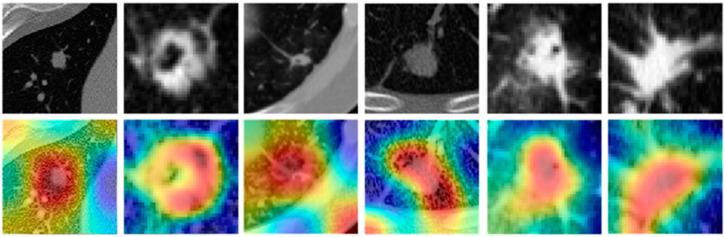

The aim of this study is to evaluate whether NIS radiomics can distinguish lung adenocarcinomas from granulomas on non-contrast CT scans, and also to improve the performance of Lung-RADS by reclassifying benign nodules that were initially assessed as suspicious. The screening or standard diagnostic non-contrast CT scans of 362 patients was divided into training (S, = 145), validation (S, = 145), and independent validation (S, = 62) sets from different institutions. Nodules were identified and manually segmented on CT images by a radiologist. A series of 264 features relating to the edge sharpness transition from the inside to the outside of the nodule were extracted. The top 10 features were used to train a linear discriminant analysis (LDA) machine learning classifier on St. In conjunction with the LDA classifier, NIS radiomics classified nodules with an AUC of 0.82 ± 0.04, 0.77, and 0.71 respectively on S, S, and S. We evaluated the ability of the NIS classifier to determine the proportion of the patients in S that were identified initially as suspicious by Lung-RADS but were reclassified as benign by applying the NIS scores. The NIS classifier was able to correctly reclassify 46% of those lesions that were actually benign but deemed suspicious by Lung-RADS alone on S.